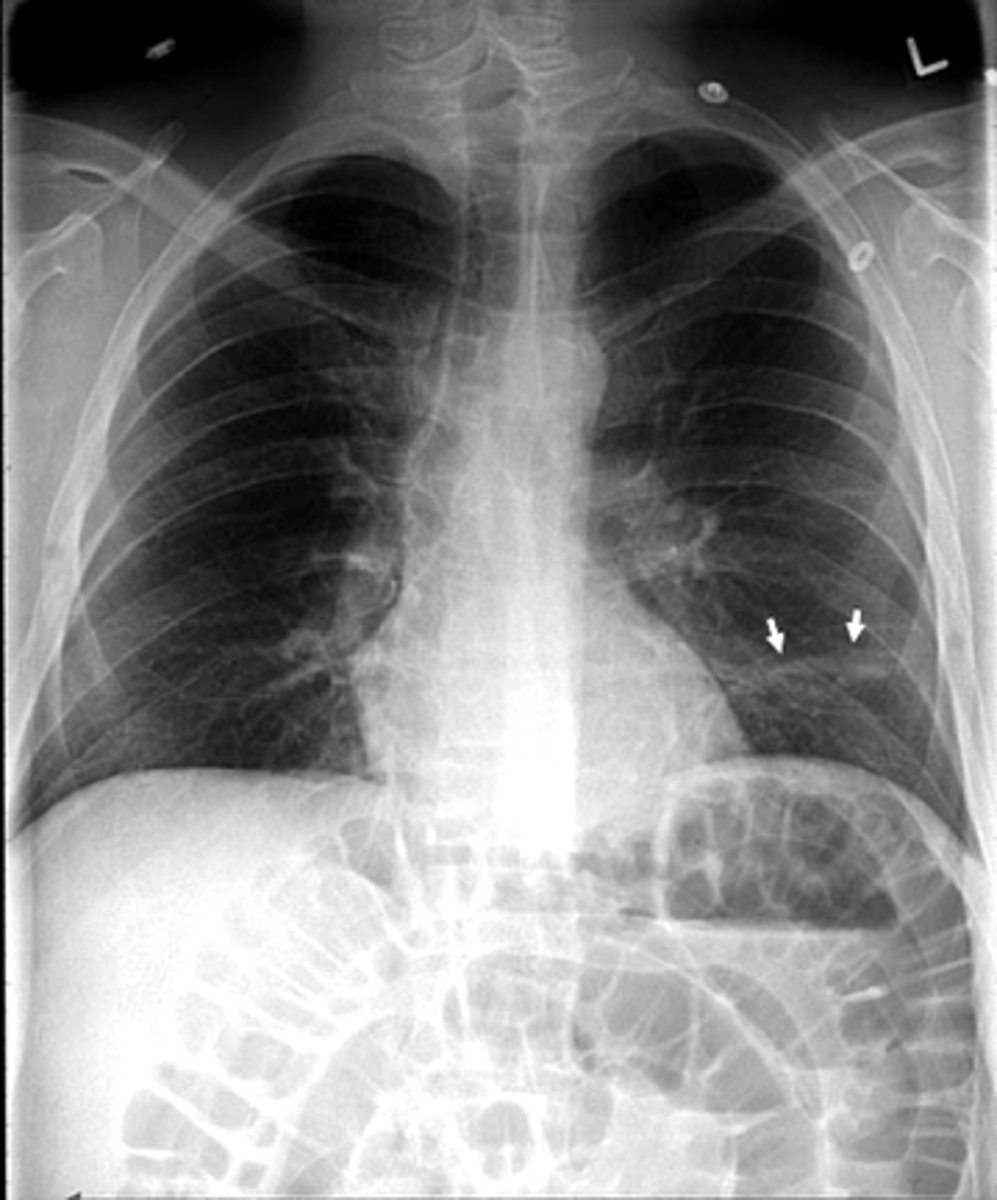

Pleural effusion

Pleural effusion

Pleural effusion (right sided)